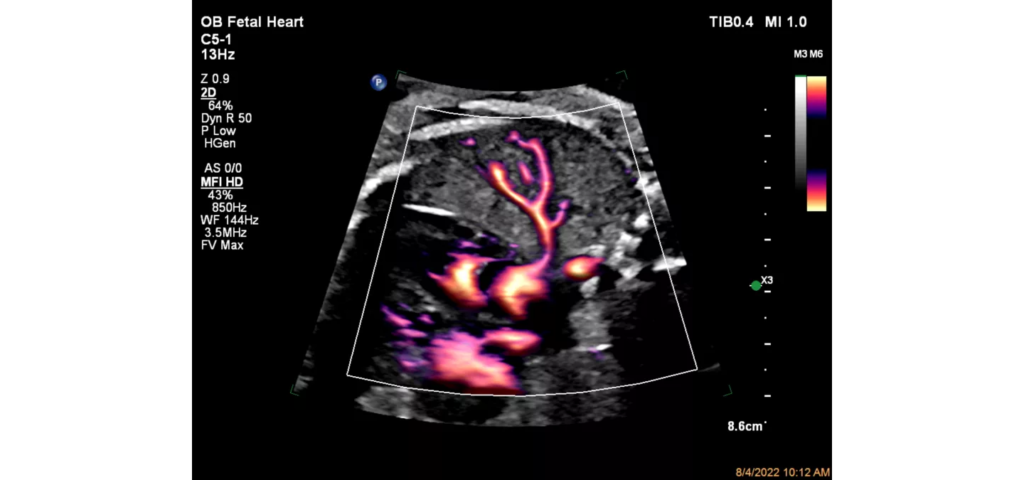

Philips EPIQ Elite ultrasound features an exceptional level of clinical performance, workflow, and advanced intelligence to meet the challenges of today’s most demanding practices. The EPIQ Elite platform brings ultimate solutions to ultrasound, with clinically tailored tools designed to elevate diagnostic confidence to new levels.